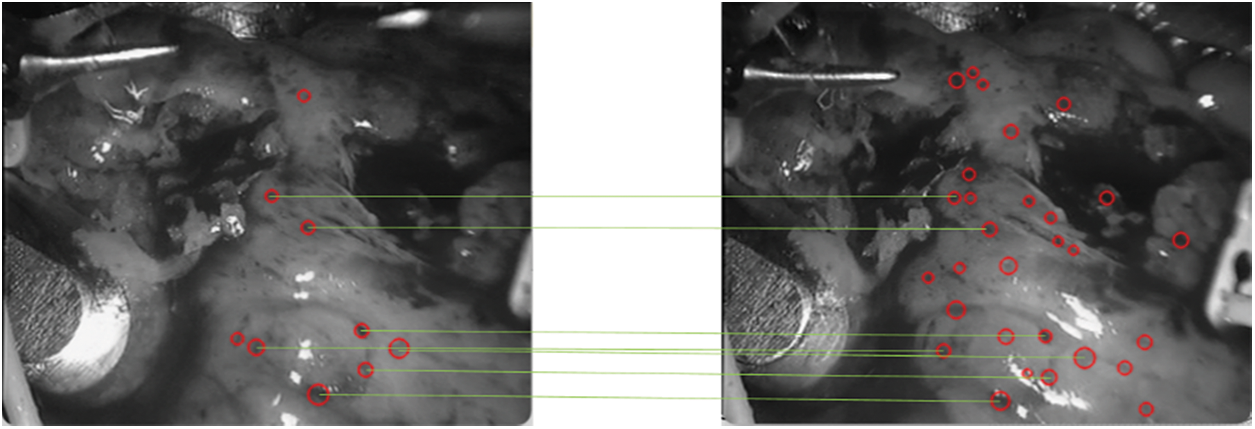

In the subsequent frames, in order to ensure the universality of the test, any frame is selected. In the experiment, any frame selected by the program is

Figure 13: Speckle matching diagram obtained by matching score matrix

As shown in Fig. 12, it can be seen that the spots detected in